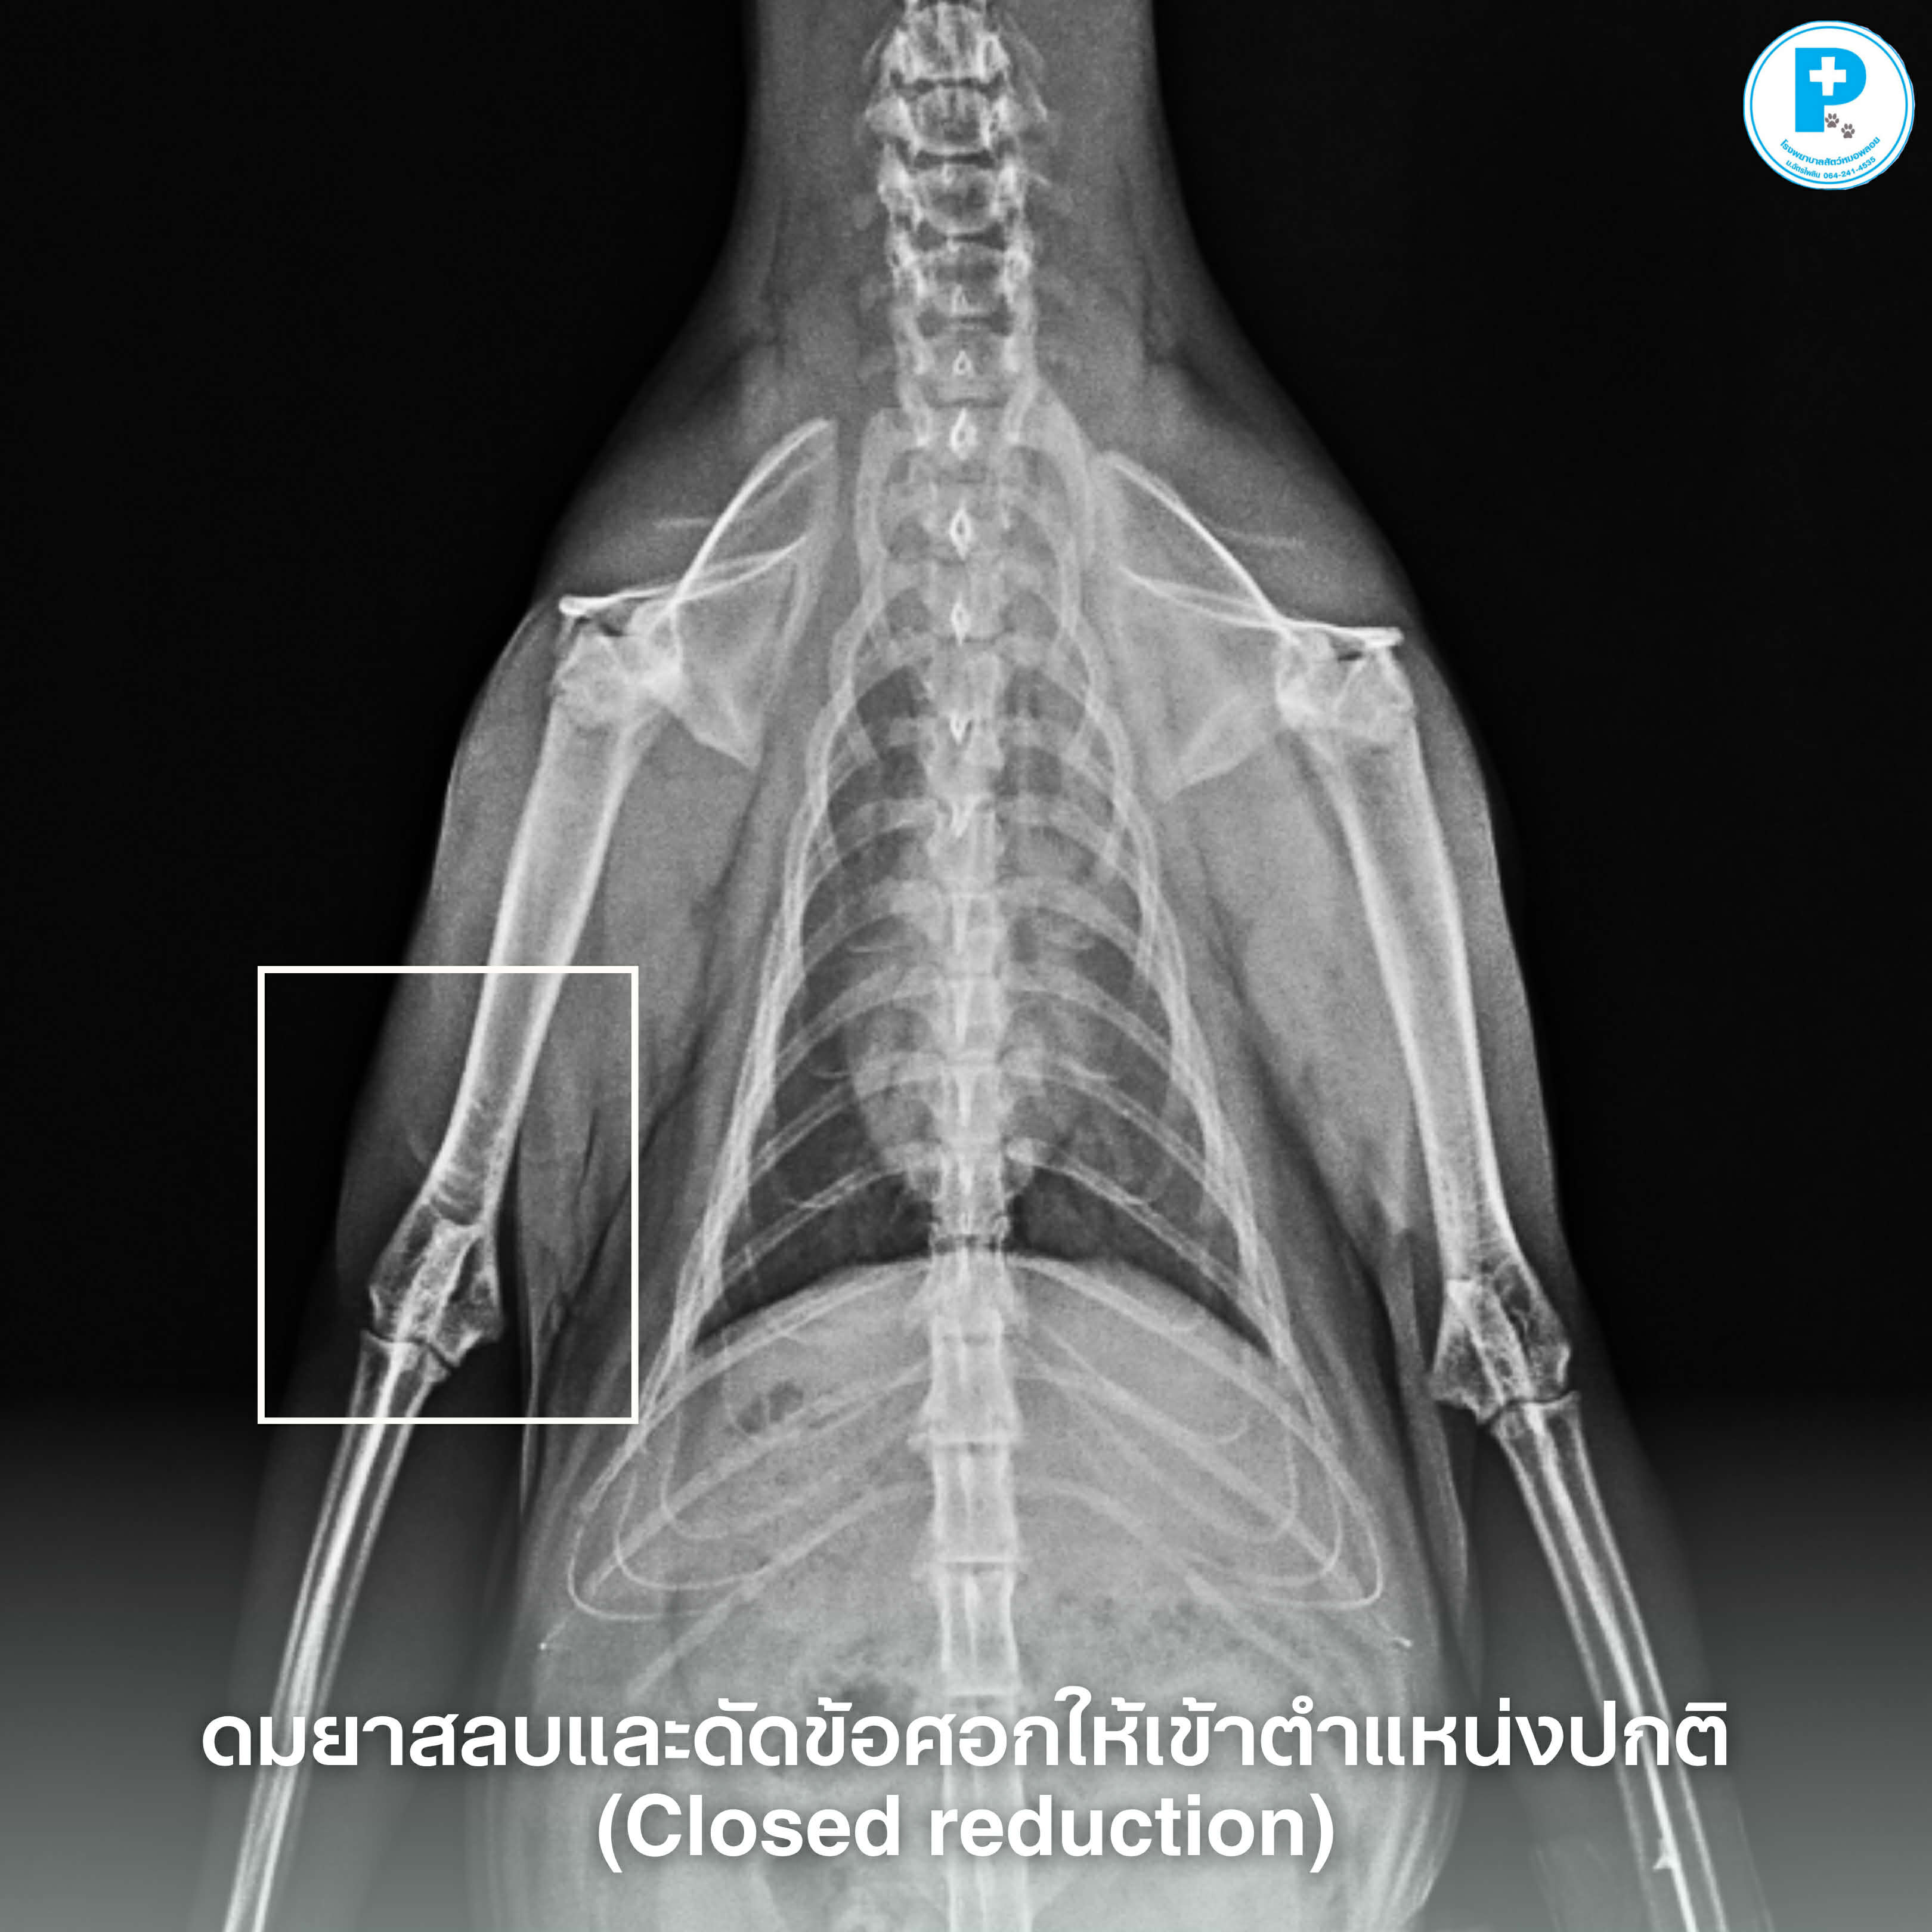

Closed reduction คือการจัดข้อให้กลับเข้าที่ภายใต้ยาสลบ เหมาะกับเคสที่เพิ่งเกิด และไม่มี fracture ร่วม

• เอกซเรย์ยืนยันและประเมินความเสียหาย

เคสนี้นอกจากข้อศอกเคลื่อน น้องยังมีบาดแผลจากอุบัติเหตุรถจักรยานยนต์ชน จึงมีการทำแผลบริเวณอื่นร่วมด้วย

หลังจัดข้อ มีการใส่เฝือกและจำกัดการเคลื่อนไหวอย่างไรก็ตาม “ระยะเวลาในการกัก/ใส่เฝือก” ต้องพิจารณาเป็นรายเคสตามความมั่นคงของข้อและการตอบสนองต่อการรักษา